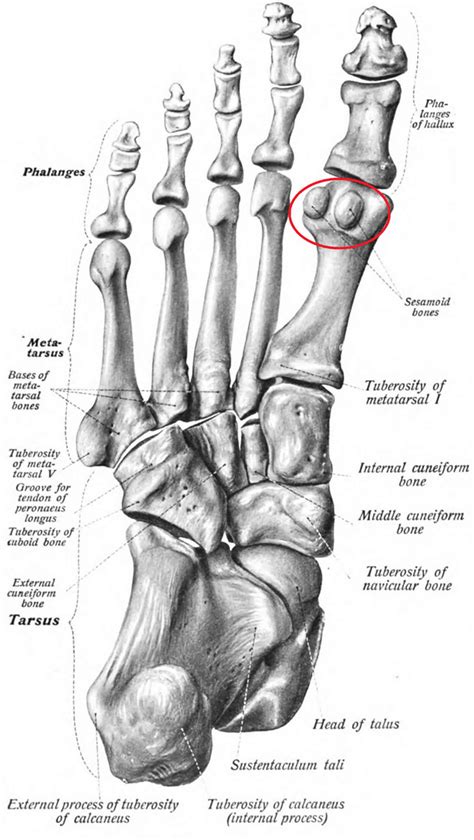

The sesamoid bones are small, round bones embedded within tendons. In the foot, there are two sesamoid bones located beneath the head of the first metatarsal bone, which is the long bone connected to the big toe. These bones are named the medial and lateral sesamoid bones, and they act as pulleys for the tendons that control the big toe.

The primary function of the sesamoid bones is to enhance the mechanical advantage of the tendons by increasing the leverage and reducing friction. This allows for more efficient movement and weight distribution during activities such as walking, running, and jumping. The sesamoid bones also help to absorb shock and distribute weight evenly across the foot.

Understanding the Sesamoid Bones